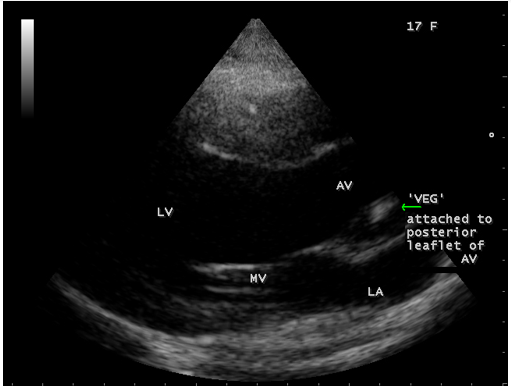

A 17-year-old female was brought to the emergency room with a history of sudden onset of breathlessness. Her pulse rate was 87 bpm and blood pressure 110/60 mmHg. She had a history of rheumatic fever during childhood, an episode of febrile illness for 10 days and taken antibiotic treatment recently. Blood chemistry revealed normal and blood cultures were negative. ECG revealed normal as shown in Figure 1 and X-ray chest revealed dilated LV (left ventricle) as in Figure 2. Physical examination revealed grade 3/6 early diastolic murmur over left mid sternal border, basal crackles over lung fields and no peripheral signs of wide pulse pressure. Transthoracic echocardiography revealed vegetations on anterior and posterior leaflets of aortic valve as in Figure 3 and Figure 4, with a “kissing-type “as in Figures 5, 6 and 8. The aortic valve was bicuspid with an attached vegetation as in Figure 9 and it was severely regurgitant as in Figure 10 and Figure 11. The left ventricle is dilated as in Figure 12 with moderate LV dysfunction as in Figure 13. The thoracic aorta was prominent as in Figure 14 with a ‘holodiastolic flow reversal’ as in Figure 15. The patient was treated with digoxin (0.25 mg, half daily), diuretics (Injection. Furosemide 20 mg IV twice daily), ACE inhibitors (tablet. Enalapril 2.5 mg twice daily) along with 2 weeks course of intravenous (IV) cefotaxime (1g) and amickacin (500mg) twice daily and advised aortic valve replacement at the earliest with lifelong penicillin prophylaxis and continuation of antibiotics for 6 weeks since the vegetations remain stable after 2 weeks of treatment, but without any embolic episodes.

Figure 4: Parasternal long axis view showing the vegetation on the posterior leaflet of aortic valve (arrow) in a 17-year old female. AV-aortic valve.